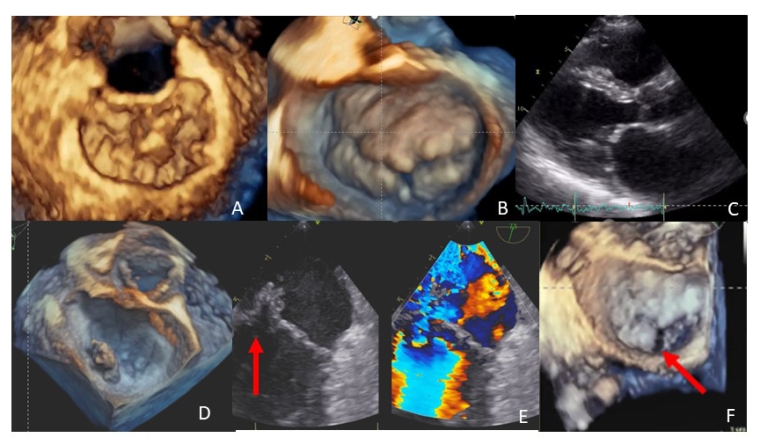

The most common aetiology is degenerative [1-2] and can be either a myxomatous degeneration or a fibroelastic deficiency (Figure 1A, Figure 1B; Video 1-2). These diseases can cause various types of lesions known as billowing, prolapse and flail. The term billowing refers to the curvature of the leaflets. It is pathological when the distance between the body of the leaflet and the annulus is more than 2 mm in a long-axis view or more than 5 mm in a 4-chamber view, considering the saddle shape of the mitral annulus. The term prolapse indicates the coaptation point above the mitral annulus. Flail is the eversion of a leaflet, generally associated with chordal rupture. Myxomatous degeneration is characterised by thickening of the leaflets, due to an excess of valve tissue and elongated chordae. When generalised, it is known as Barlow's disease.

Rheumatic mitral disease is characterised by a variable thickening of the leaflets, which occurs especially at the free margin, commissural fusion and a systolic-diastolic movement restriction (Figure 1C; Video 3). Fibrosis of the chordae tendineae is also common. Two types of rheumatic MR can be distinguished. In one form, the fibrosis affects the chordae tendineae afferent to both leaflets, which are hypomobile. In the other form, fibrosis mainly affects the chordae afferent to the posterior leaflet, causing a pseudo-prolapse of the anterior leaflet [3].

Libman–Sacks endocarditis is a form of abacterial endocarditis, also called marantic endocarditis. It is found in association with inflammatory diseases, such as systemic lupus erythematosus, antiphospholipid antibody syndrome and cancer. The vegetations are usually small and are located mainly at the level of the basal and middle portions of the leaflets (Figure 1D; Video 4). Infective endocarditis is recognised by the presence of vegetations, leaflet perforation or perivalvular abscesses (Figure 1E; Video 5) [4].

Congenital forms of MR are cleft (indentation of the leaflet that extends more than 50% of the depth of the leaflet) (Figure 1F; Video 6) and "parachute mitral valve" (when all the chordae originate from a single papillary muscle) [5].

Panel A and Video 1. Fibroelastic deficiency with prolapse and flail of P2 (3D “en face” view); Panel B and Video 2. Myxomatous degeneration (3D “en face” view); Panel C and Video 3. Rheumatic disease (parasternal long-axis view); Panel D and Video 4. Marantic vegetation on posterior annulus (3D “en face” view); Panel E and Video 5. MR due to endocarditis and leaflet perforation (2-chamber view on TOE, red arrow); Panel F and Video 6. Cleft of the posterior leaflet (3D “en face” view, red arrow).